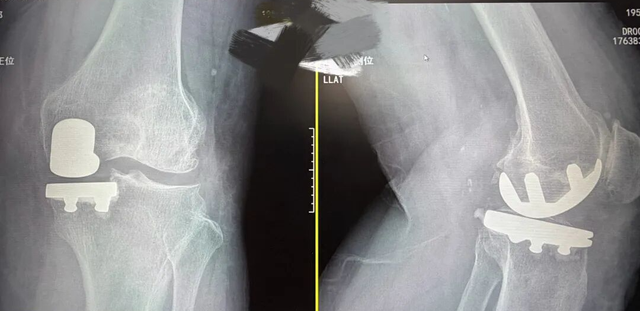

手术后:

经过完善的术前准备,在手术室、麻醉科等科室的通力配合下,李奶奶的手术顺利完成。术后第一天,骨科康复治疗师跟进后续康复治疗,帮助李奶奶进行术后康复。